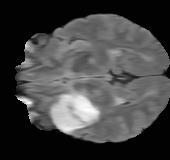

As we observe from the right image in Fig. 2, our BRM, both from MIMO and SISO settings, predicts the performance of dedicated models with a high correlation. We further choose the best three , and perform the last stage of fine-tuning accordingly to (6). A visual evaluation on real data is shown in Fig. 3. For simulated data, please refer to the Supplemental Material section.

Base on the best performing , we perceive that among , , and FLAIR, the results are best when is sampled the most. We suggest that this makes intuitive sense as images provide the best contrast out of the three sequences, which can compensate for the details lost in other images. The same observation can be made on the simulated data, where both and FLAIR show good contrast. When the time setting is changed to non-uniformity, we can see that our search for the best sampling strategy reflects the change. is sampled more as a result of faster acquisition time, while is still sufficiently sampled.

| Sequence | LR | SISO | MIMO | MIMO tuned | GT |

|---|---|---|---|---|---|

|

(k) 39.89/0.9311

(k) 39.89/0.9311

|

(l) 43.94/0.9864

(l) 43.94/0.9864

|

(m) 44.74/0.9883

(m) 44.74/0.9883

|

(n) 45.49/0.9894

(n) 45.49/0.9894

|

(o) PSNR/SSIM

(o) PSNR/SSIM

|